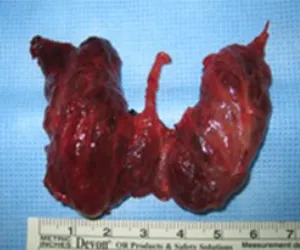

갑상선은 좌엽과 우엽, 그리고 연결부위인 협부로 이루어져 있습니다.

갑상선암이 있는 위치, 크기에 따라 수술 범위를 정하는데, 대개 갑상선전절제술(전절제)과

갑상선엽절제술(반절제)로 나눌 수

있습니다.

드물게, 갑상선암이 협부에만 조그맣게 있는 경우에는 갑상선 협부만 절제하는 갑상선협부절제술을 시행하기도 합니다.

갑상선전절제 상태

갑상선 여포성종양으로

갑상선반절제를 한 상태

갑상선종 (갑상선이

전반적으로 커져 있다)

커다란 갑상선여포암으로

갑상선전절제한 상태